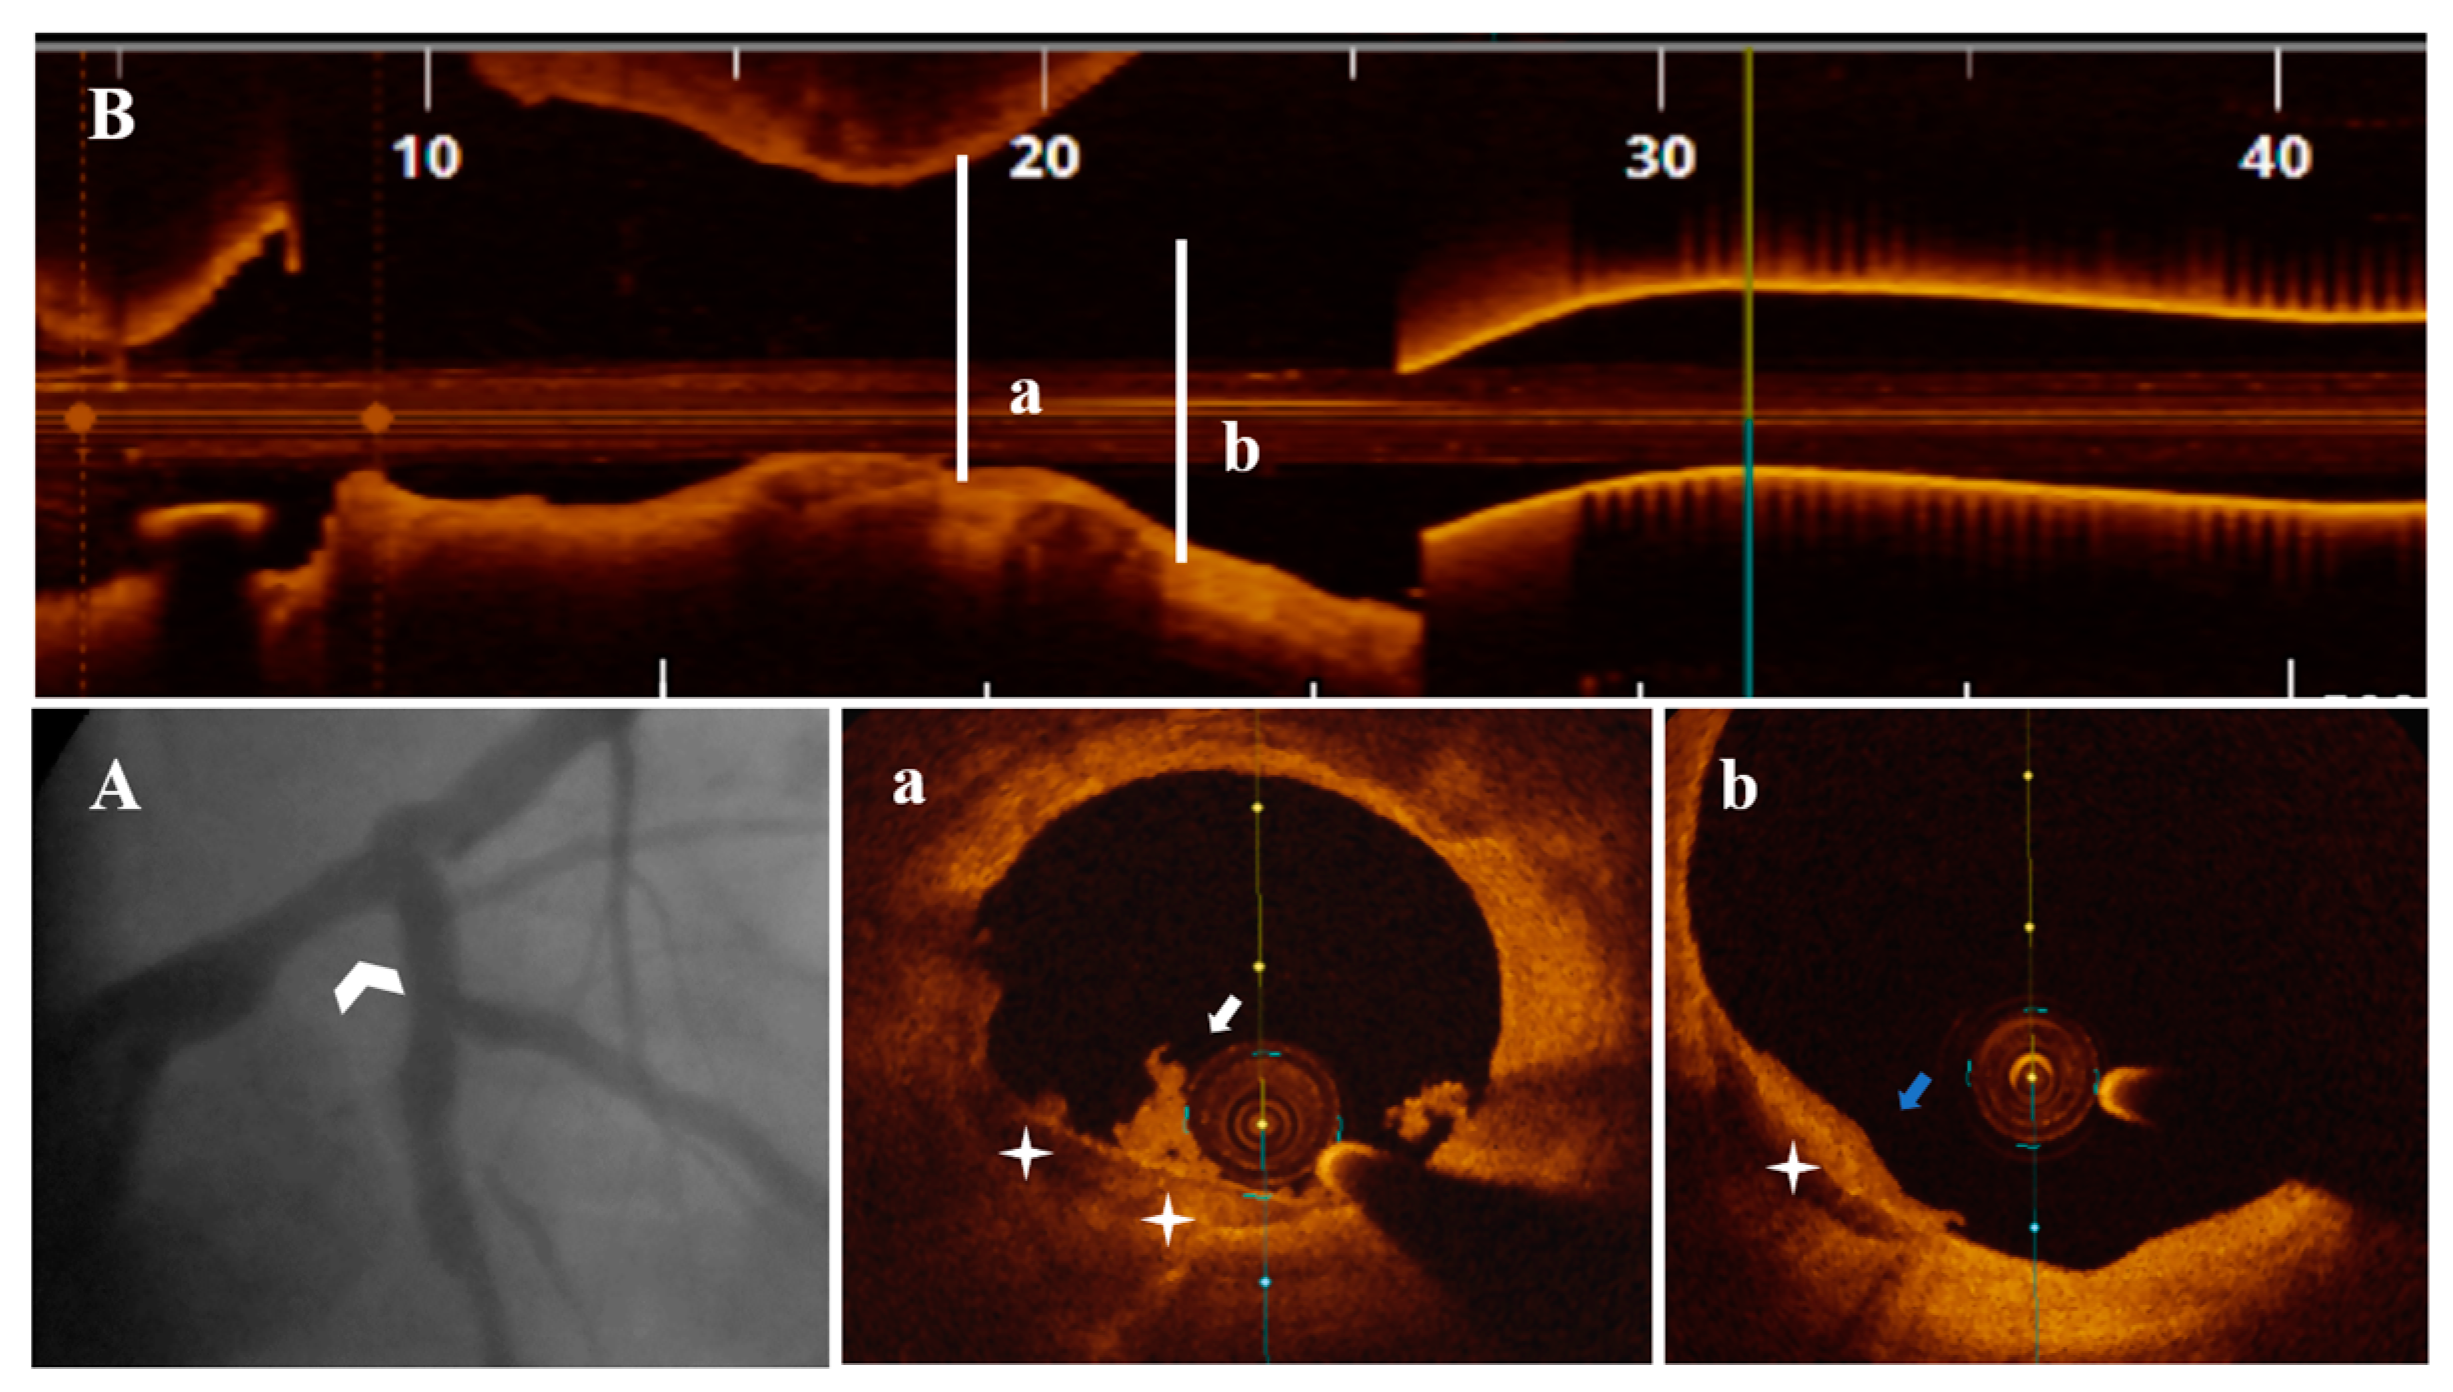

Figure 3.

A 51-year-old patient presenting with NSTEMI. (A) CA—borderline mid-distal LM stenosis (white arrowhead). (B) OCT—LM plaque longitudinal view. (a,b) OCT—transversal view, nonsignificant mid-LM plaque (area stenosis = 42.9%) presenting PE with white thrombi (white arrow) on SCP (white star) extending proximally in interrelation with a healed plaque (blue arrow).